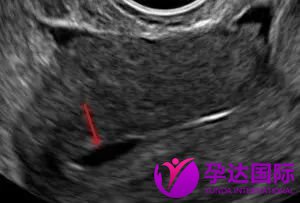

经大量研究发现,子宫内膜超声形态(包括子宫内膜厚度、回声、血流等)是判断胚胎移植的种植窗口期的一个重要的评估指标。超声波显示正常子宫内膜种植窗时期厚度一般约在7-10mm之间,容积不应该小于2ml且内膜能量多普勒面积多在5㎜以上。

子宫内膜细胞不断产生液体。这些液体中的一些被子宫内膜中的细胞重吸收,一些液体从子宫通过子宫颈渗漏到阴道中,一些泄漏物被认为是输卵管进入腹部。然而,在一些情况下,额外的流体可能积聚在腔体中,这可以在超声波上看到。医生不希望将胚胎移植到充满液体的子宫腔中,因为这将减少胚胎植入的机会。